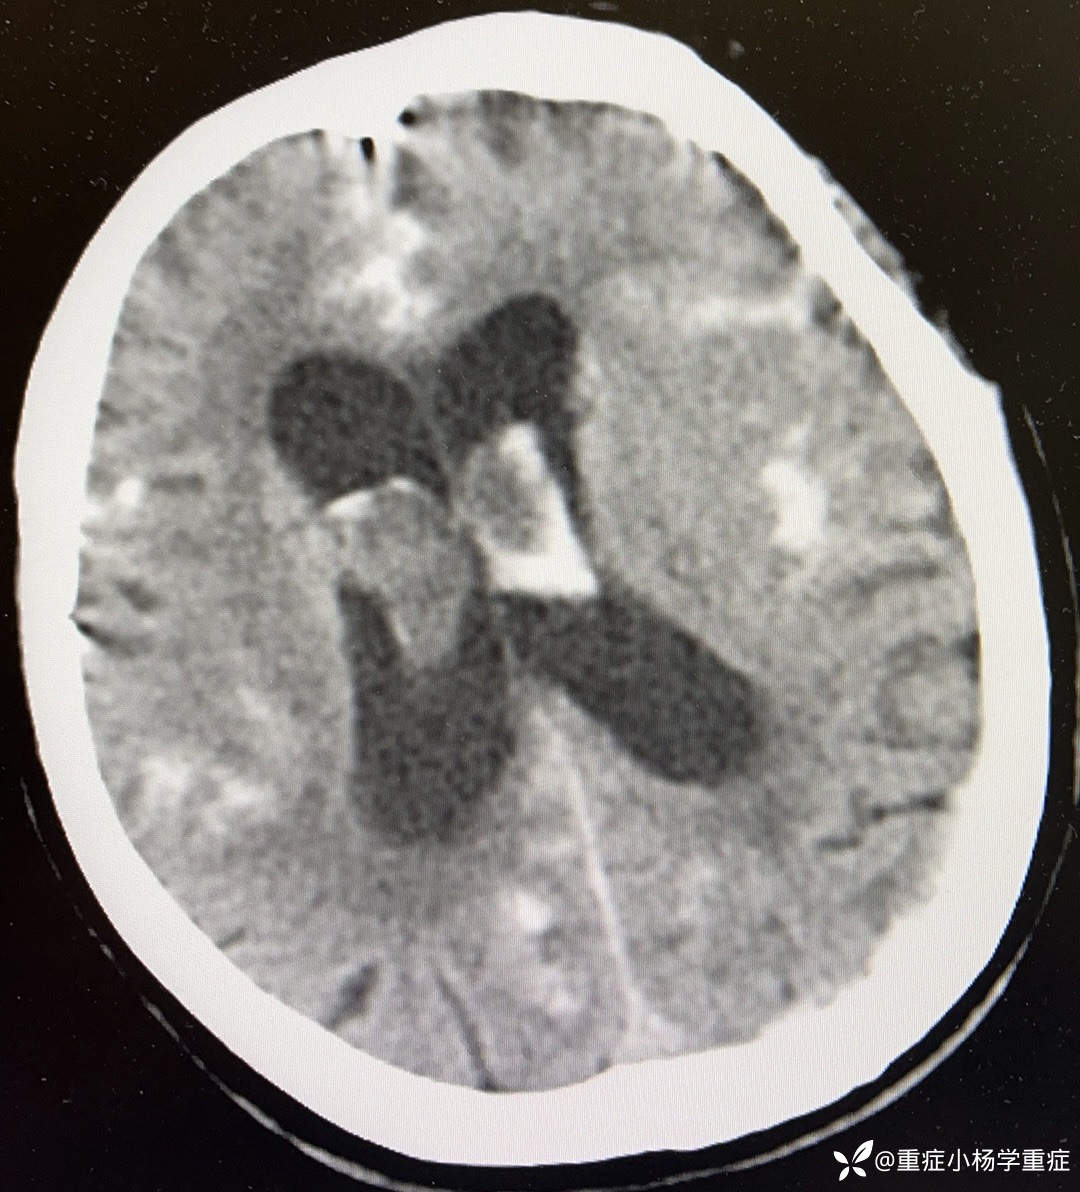

简要病史:患者于7小时余前吃中饭时突发意识不清,头撞到桌面,呼之不应,无抽搐,家属拨打120送我院急诊,测脉搏105次/分,呼吸14次/分,血压:207/92mmHg,SPO2 95%,至急诊后出现呕吐2次,为胃内容物,行CT检查提示:蛛网膜下腔出血破入脑室系统;予以氨甲环酸止血、尼莫地平防止脑血管痉挛、乌拉地尔控制血压,请神经外科会诊考虑“动脉瘤破裂出血”建议行CTA明确诊断及手术治疗,患者家属经商讨后拒绝CTA检查及手术治疗,要求行保守治疗,经我科会诊后以“蛛网膜下出血、脑血管意外、高血压”收住院治疗。

辅助检查:生化:肌酐128.9umol/L↑,钠146.3mmol/L↑。CT平扫:1.蛛网膜下腔出血破入脑室系统;2.老年脑改变;3.考虑两肺少许炎症,随诊复查。